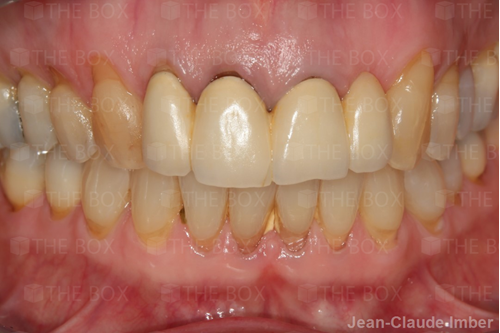

A new case was made public by Jean-Claude Imber check it out here.